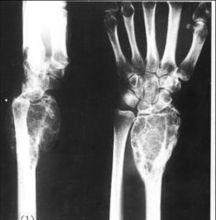

3.X線檢查應注意骨破壞範圍、程度及界限,有無骨膜反應,有無瘤骨形成及有無軟組織陰影。必要時應行CT、MRI檢查及血管造影。